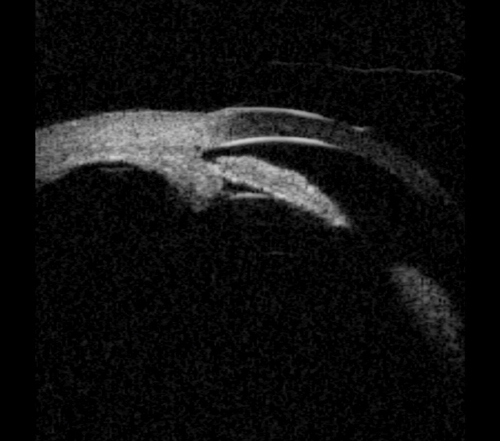

Plateau iris configuration is associated with an abnormally short iris root, which is anteriorly inserted in the ciliary body and pushes the iris against the trabecular meshwork. Typically the angle becomes steeply rising, and irido trabecular contact occurs particularly in the dark. Centrally, the anterior chamber appears deep and the iris profile is flat. Plateau iris occurs with a deep central anterior chamber and an occludable angle on gonioscopy. Plateau iris syndrome may be diagnosed following a laser iridotomy, where the pressure remains high even though the peripheral iridotomy (PI) has eliminated the relative pupillary block.

Figure 2a: Plateau iris. Sectoral UBM images in photopic conditions showing flat iris plane,

deep central PAC, anteriorly positioned ciliary sulcus, and angular iris root.

Figure 2b: Plateau iris - dark adaptation showing irido trabecular contact.

The diagnosis of plateau iris can be made by UBM and is characterised by: an angular iris root which is steeply rising combined with a flat iris plane and anterior rotation of the ciliary body (or processes). Indeed, UBM has indicated that plateau iris is more common than previously thought, and occurs in at least 50% of PAC(G) cases. UBM has been shown to identify patients with intermittent angle closure previously diagnosed as open angle glaucoma.